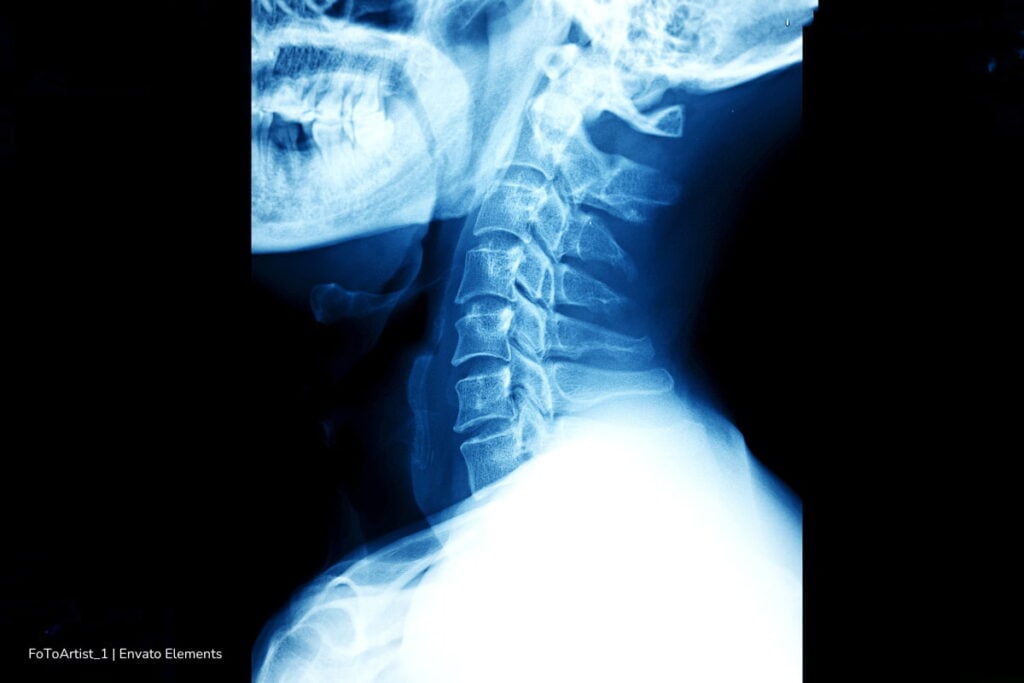

Los exámenes médicos mostraron alteraciones en las vértebras del cuello, desplazamientos y acumulación de tejido cicatricial. La columna se había adaptado a una posición incorrecta durante años.

En un inicio, se intentó tratar el problema con collarines, pero no funcionó. Finalmente, los médicos optaron por cirugía para corregir el daño causado por el síndrome de cabeza caída.

El procedimiento incluyó el retiro de partes dañadas de las vértebras, la eliminación de tejido cicatricial y el uso de tornillos y varillas para estabilizar el cuello. Tras la intervención, el paciente logró recuperar la movilidad. Sin embargo, los especialistas insistieron en que no todos los casos tienen el mismo desenlace.